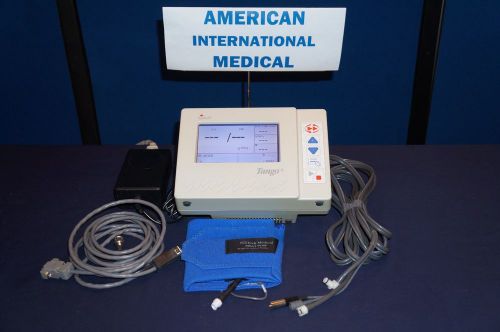

Suntech Tango Plus Blood Pressure Monitor (Refurbished)